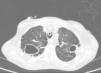

Chest radiograph revealed fibrocavitary tracts in both upper fields with signs of air trapping, confirmed on CT (Fig. 1). No particular findings were revealed in the head or the abdomen. Fiberoptic bronchoscopy was performed, showing signs of inflammation of the bronchial mucosa, and bronchial aspirates were obtained for standard and mycobacterial culture. Standard culture techniques showed growth of saprophytic flora, with no Legionella spp. or fungal strains. No alcohol-acid resistant bacilli (AARB) were observed on Ziehl-Neelsen staining. A serology study for HIV and IgM antibodies against Mycoplasma pneumoniae, Coxiella burnetii, Chlamydophila pneumoniae, Legionella pneumoniae and anti-Chlamydophila psittaci indirect immunofluorescence were negative. Blood cultures and Mantoux were also negative.